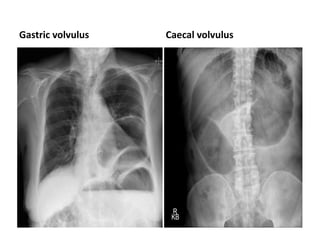

Gastric volvulus

• Spherical viscus

• Displaced upwards & to

the left

• Raised left

hemidiaphargm

• Contains both air and

fluid

• Usually no gas in bowel

beyond stomach

Gastric volvulus Caecal volvulus

Gastric volvulus • Sphericalviscus • Displaced upwards & to the left • Raised left hemidiaphargm • Contains both air and fluid • Usually no gas in bowel beyond stomach

• 69.

Volvulus • Twisting ofthe bowel, or volvulus, is a specific cause of bowel obstruction which can have characteristic appearances on an abdominal X- ray. • The two commonest types of bowel twisting are sigmoid volvulus and caecal volvulus.

• Caecal volvulus •The caecum is most frequently a retroperitoneal structure, and therefore not susceptible to twisting. However, in up to 11% of individuals there is congenital incomplete peritoneal covering of the caecum with formation of a 'mobile' caecum on a mesentery, such that it no longer lies in the right iliac fossa. This is a normal variant but is associated with increased incidence of folding or twisting of the caecum (caecal volvulus), which may be complicated by obstruction, vascular compromise, or perforation.